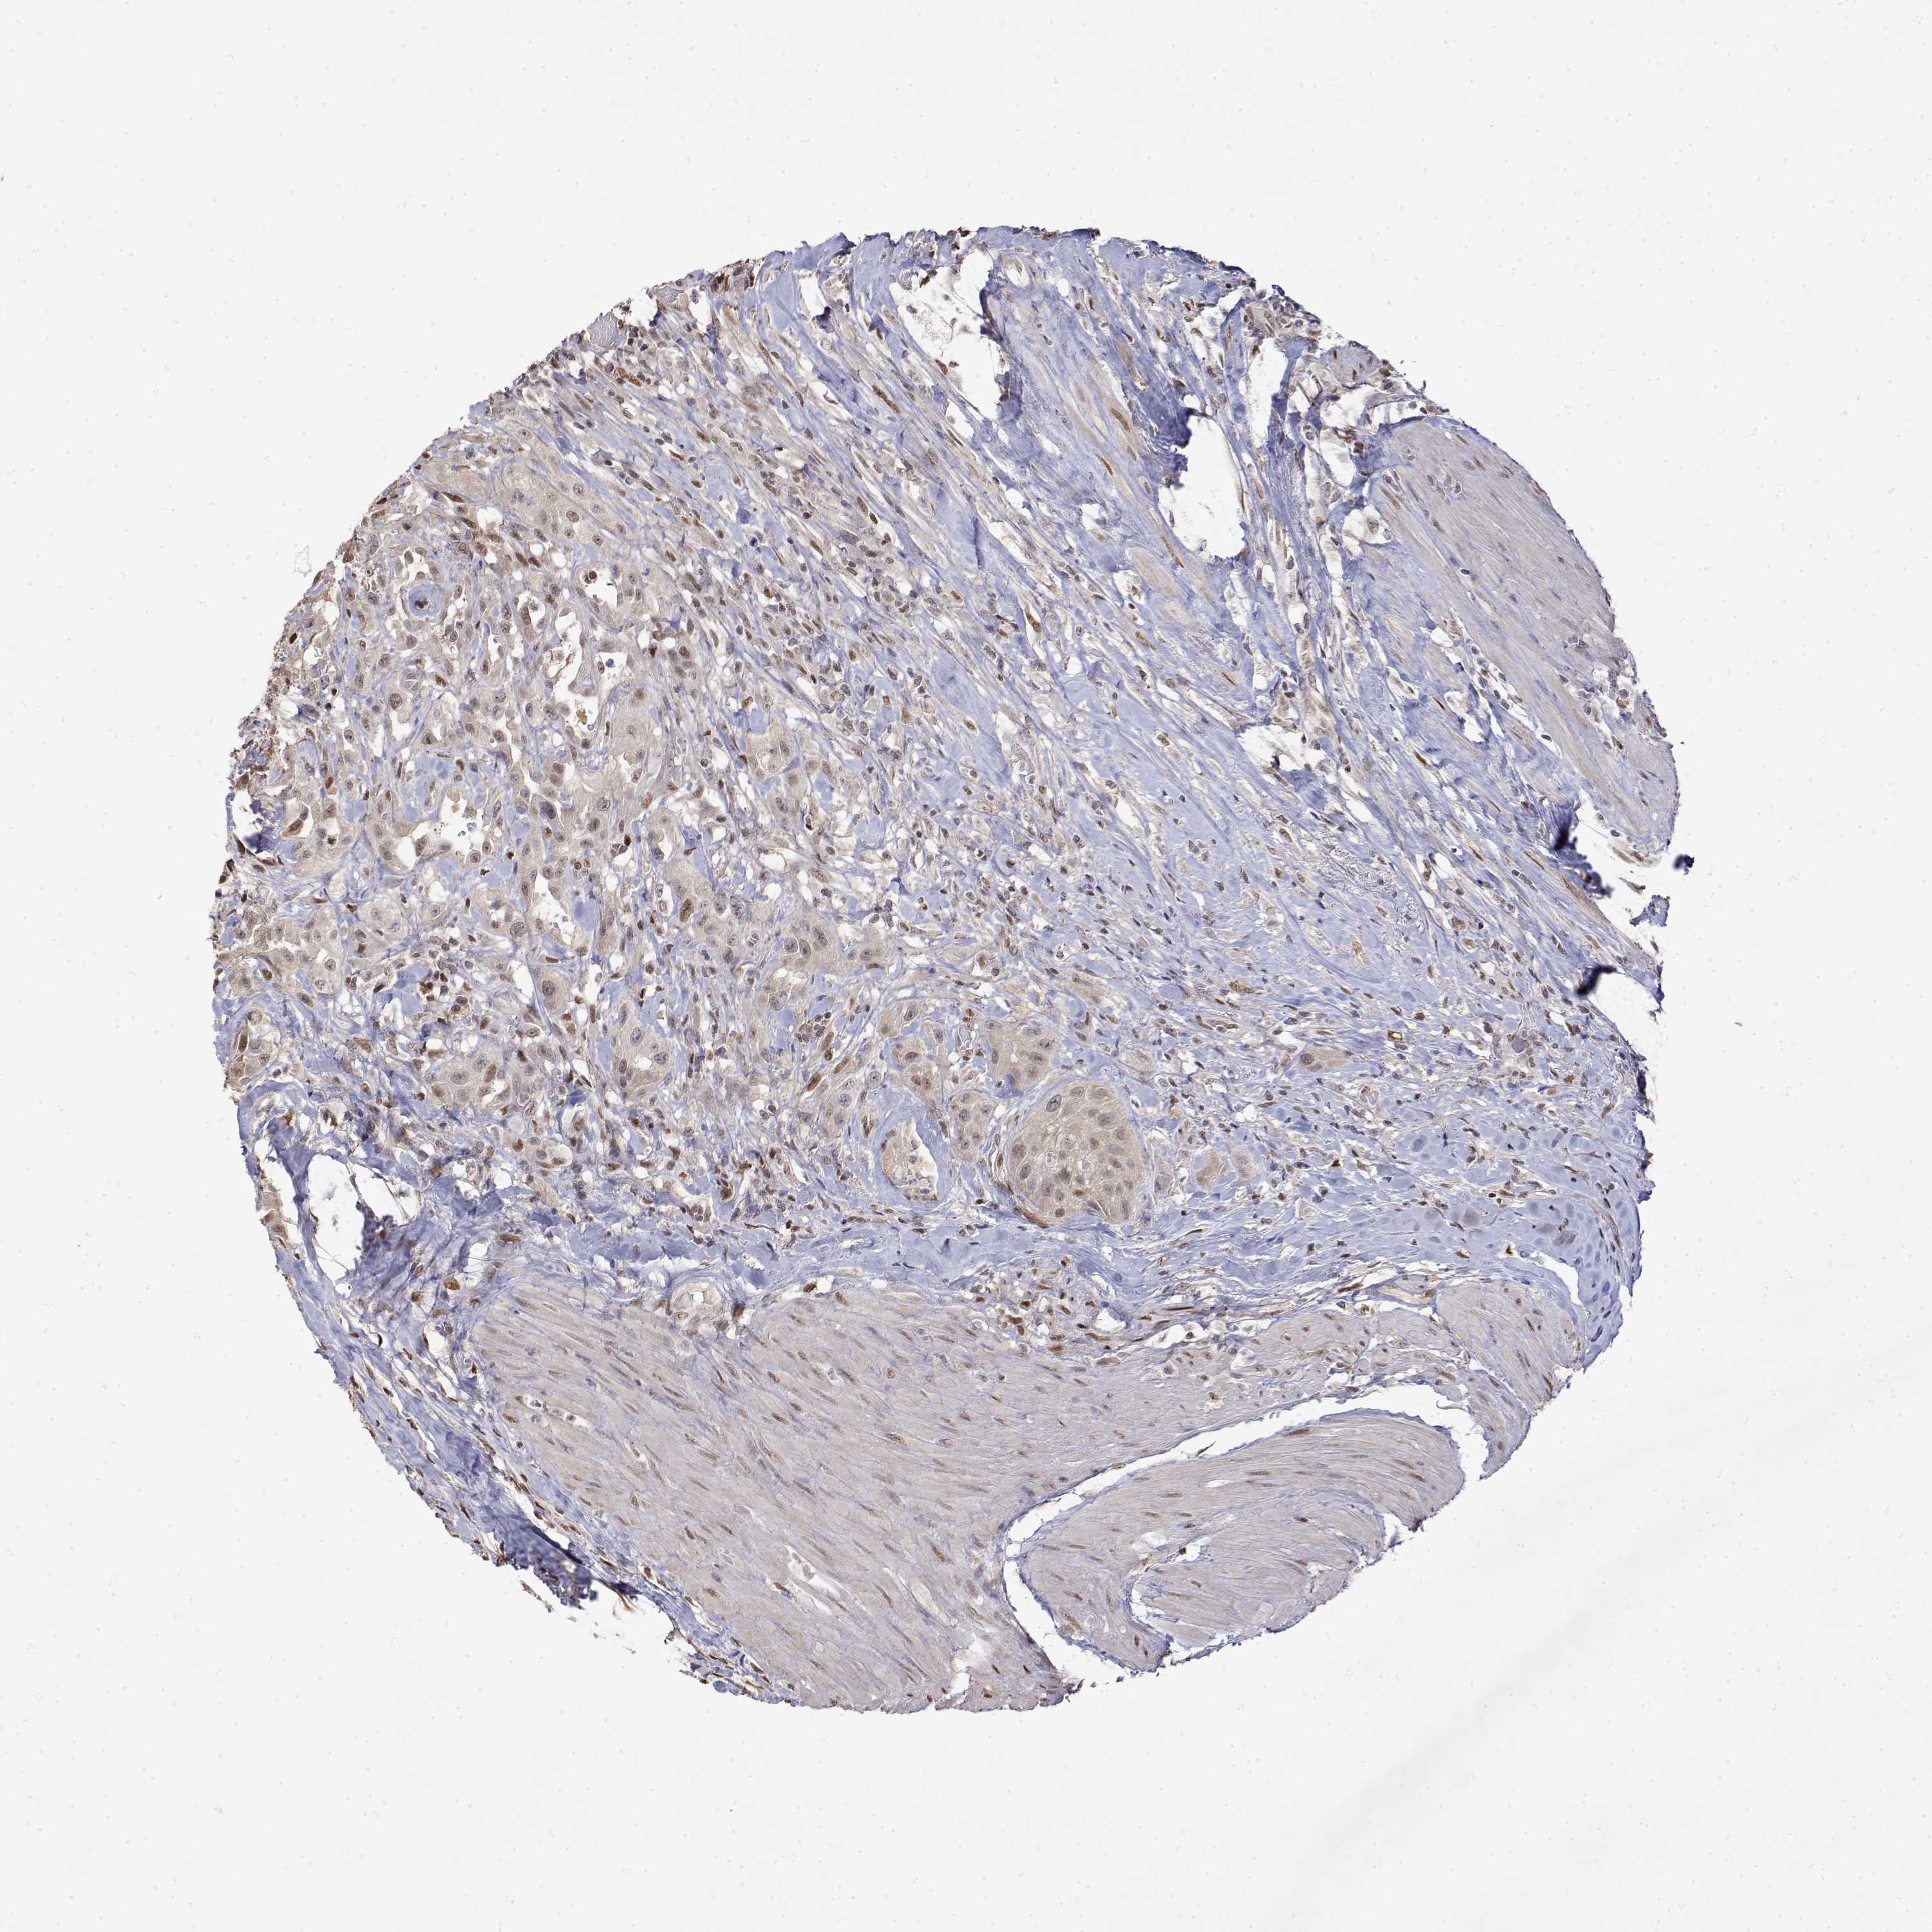

UROTHELIAL CANCER - Protein expressioni

A mouse-over function shows sample information and annotation data. Click on an image to view it in a full screen mode. Samples can be filtered based on level of antibody staining by selecting one or several of the following categories: high, medium, low and not detected. The assay and annotation is described here.

Note that samples used for immunohistochemistry by the Human Protein Atlas do not correspond to samples in the TCGA dataset.

Antibody stainingi

Antibody staining in the annotated cell types in the current human tissue is reported as not detected, low, medium, or high, based on conventional immunohistochemistry profiling in selected tissues. This score is based on the combination of the staining intensity and fraction of stained cells.

Each image is clickable and will lead to virtual microscopy that enables deeper exploration of all samples and also displays staining intensity scores, fraction scores and subcellular localization as well as patient and tissue information for each sample.

Antibody HPA050924

Antibody HPA053568

Staining

High

Medium

Low

Not detected

Intensity

Strong

Moderate

Weak

Negative

Quantity

>75%

75%-25%

<25%

None

Location

Nuclear

Cytoplasmic/membranous

Cytoplasmic/membranous,nuclear

Urothelial carcinoma, High grade

Urothelial carcinoma, NOS

Urothelial carcinoma, Low grade